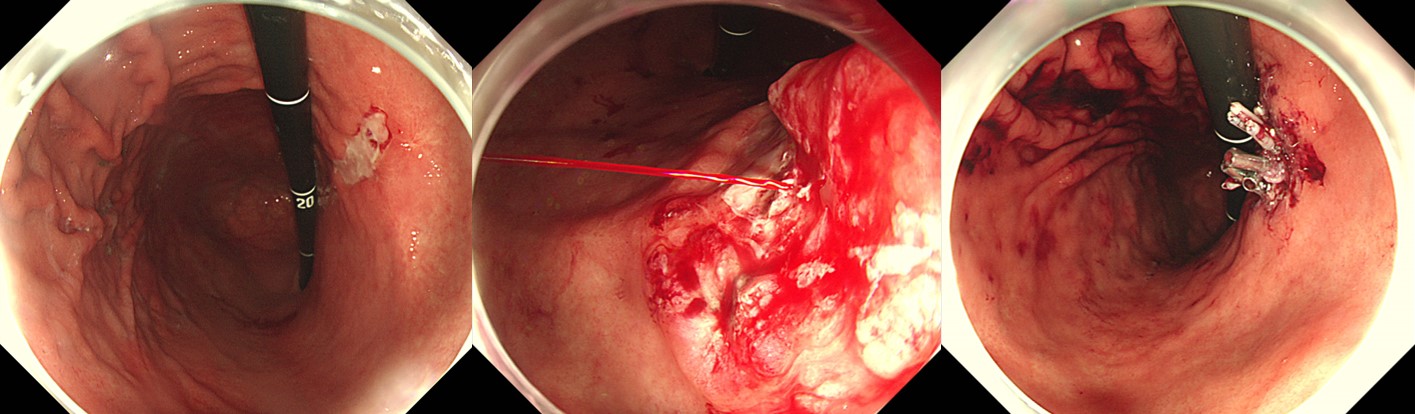

Exposed vessel ÁöÇ÷¼ú Áß spurtingÀÌ º¸¿© ÀÏȸ¿ë clipÀ» ÀÌ¿ëÇÑ ÁöÇ÷¼úÀ» ½ÃµµÇÏ¿´À¸³ª ±Ë¾çÀú°¡ ¸Å¿ì ´Ü´ÜÇÏ¿© ¹Ì²ô·¯Áö±â¸¸ Çϰí Á¤È®ÇÑ targetingÀÌ µÇÁö ¾Ê¾Æ Olympus EZ clipÀ¸·Î ¹Ù²ã ¸î ¹ø ´õ ½ÃµµÇÑ ÈÄ ÁöÇ÷ÀÌ µÊ